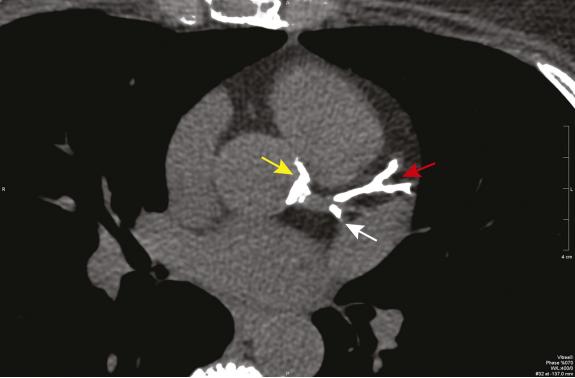

Severe calcification of the left anterior descending coronary artery (red arrow), the portion of the circumflex coronary artery within the imaging plane (white arrow), and the aortic root around the origin of the left main coronary artery (yellow arrow).